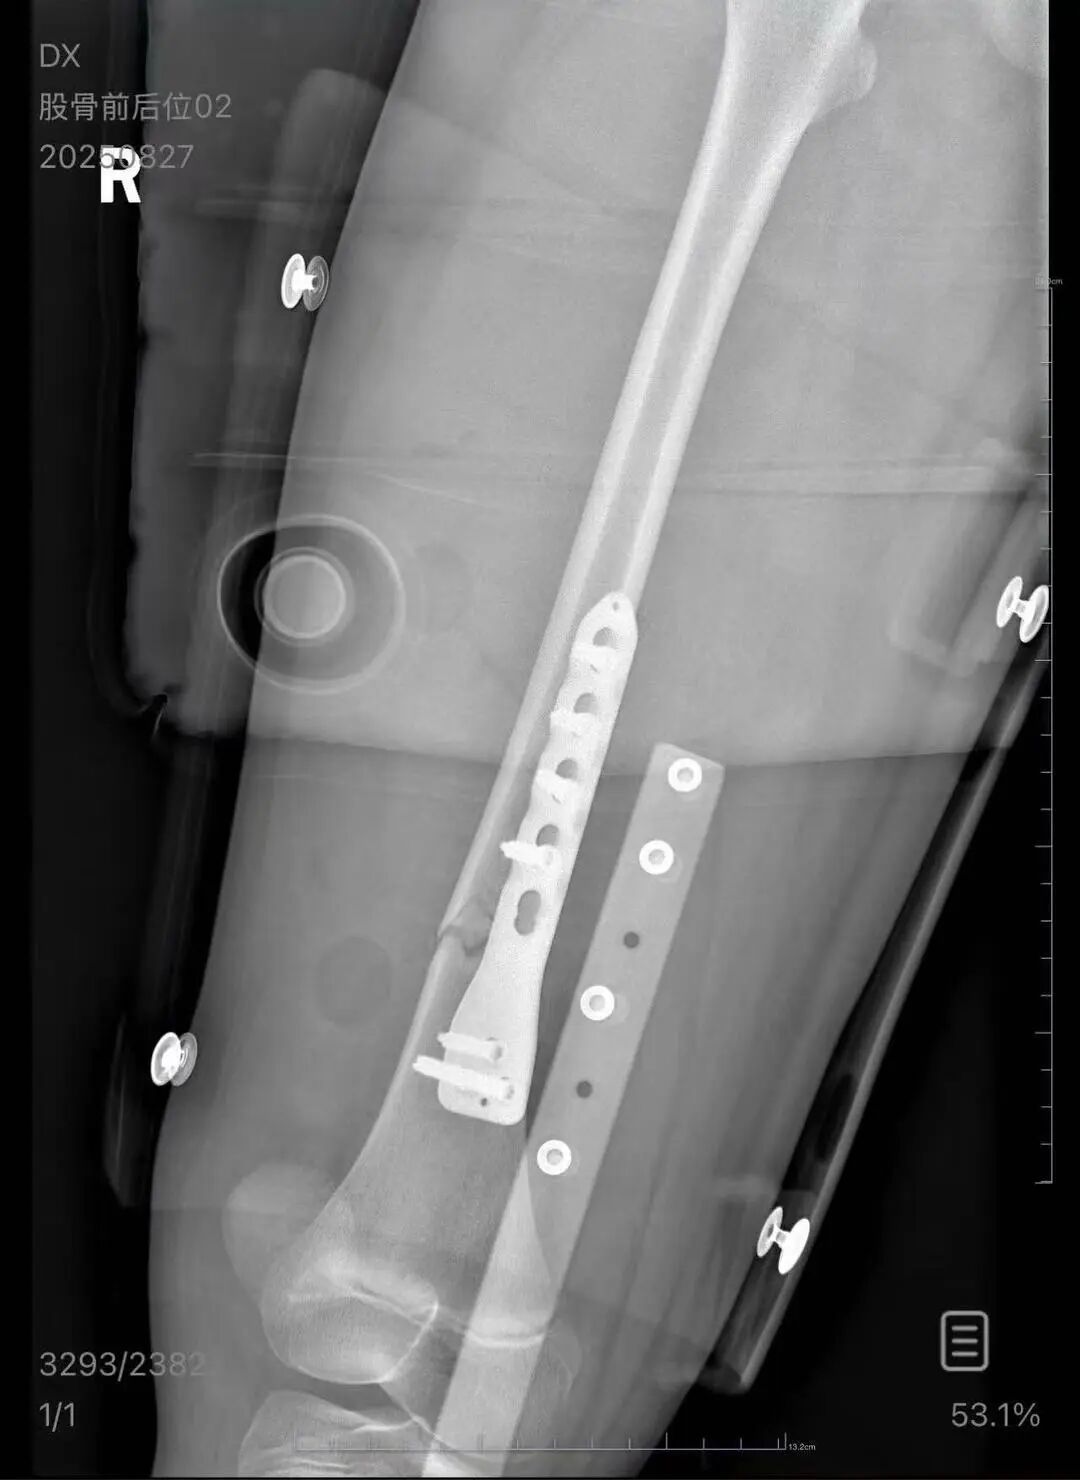

朱女士向记者出示的医院病历显示,8月24日凌晨,朱女士的女儿到医院就诊。医院诊断朱女士的女儿右股骨骨折,需要住院进一步治疗。

▲朱女士女儿手术后拍的X光片 受访者供图

朱女士出示的报警回执显示,8月24日凌晨2点22分,上海铁路公安处无锡站派出所接到报案。报案人称,在某列车上,快要到无锡站时,上铺的乘客下床时没抓稳,导致孩子大腿骨折。